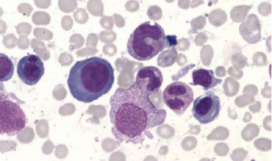

Онкология >

Программа предусматривает совершенствование теоретических знаний и практических навыков по диагностике и лечению детей с лейкозами, обеспечивающих ...

Гематология >